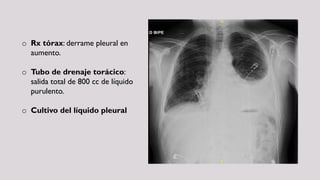

o Rx tórax: derrame pleural en

aumento.

o Tubo de drenaje torácico:

salida total de 800 cc de líquido

purulento.

o Cultivo del líquido pleural